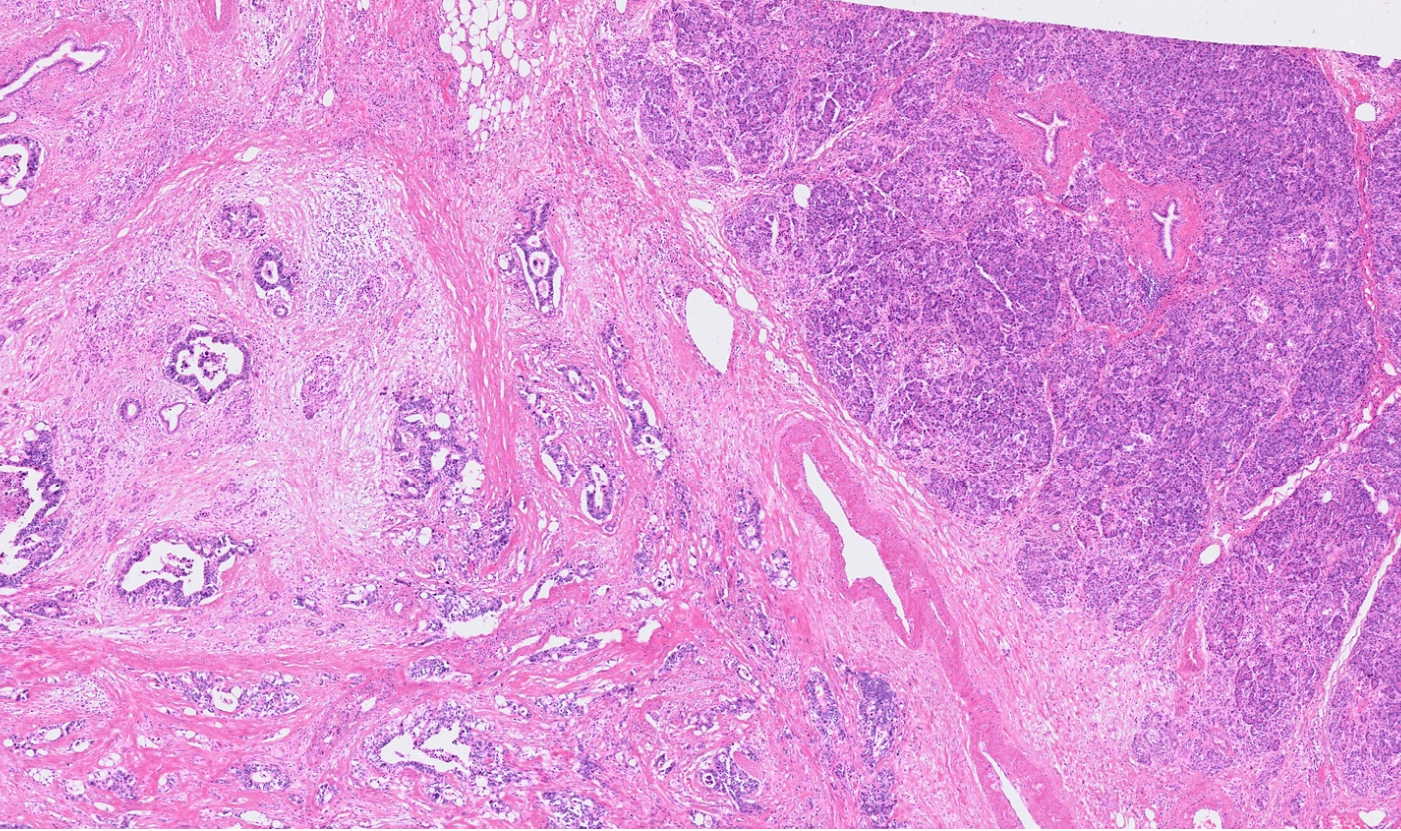

Applicability across many tissue types

The segmentation module is designed to generalize across a wide range of biological tissues. Below are representative benchmark results based on 10x Genomics demo datasets:

Ovary